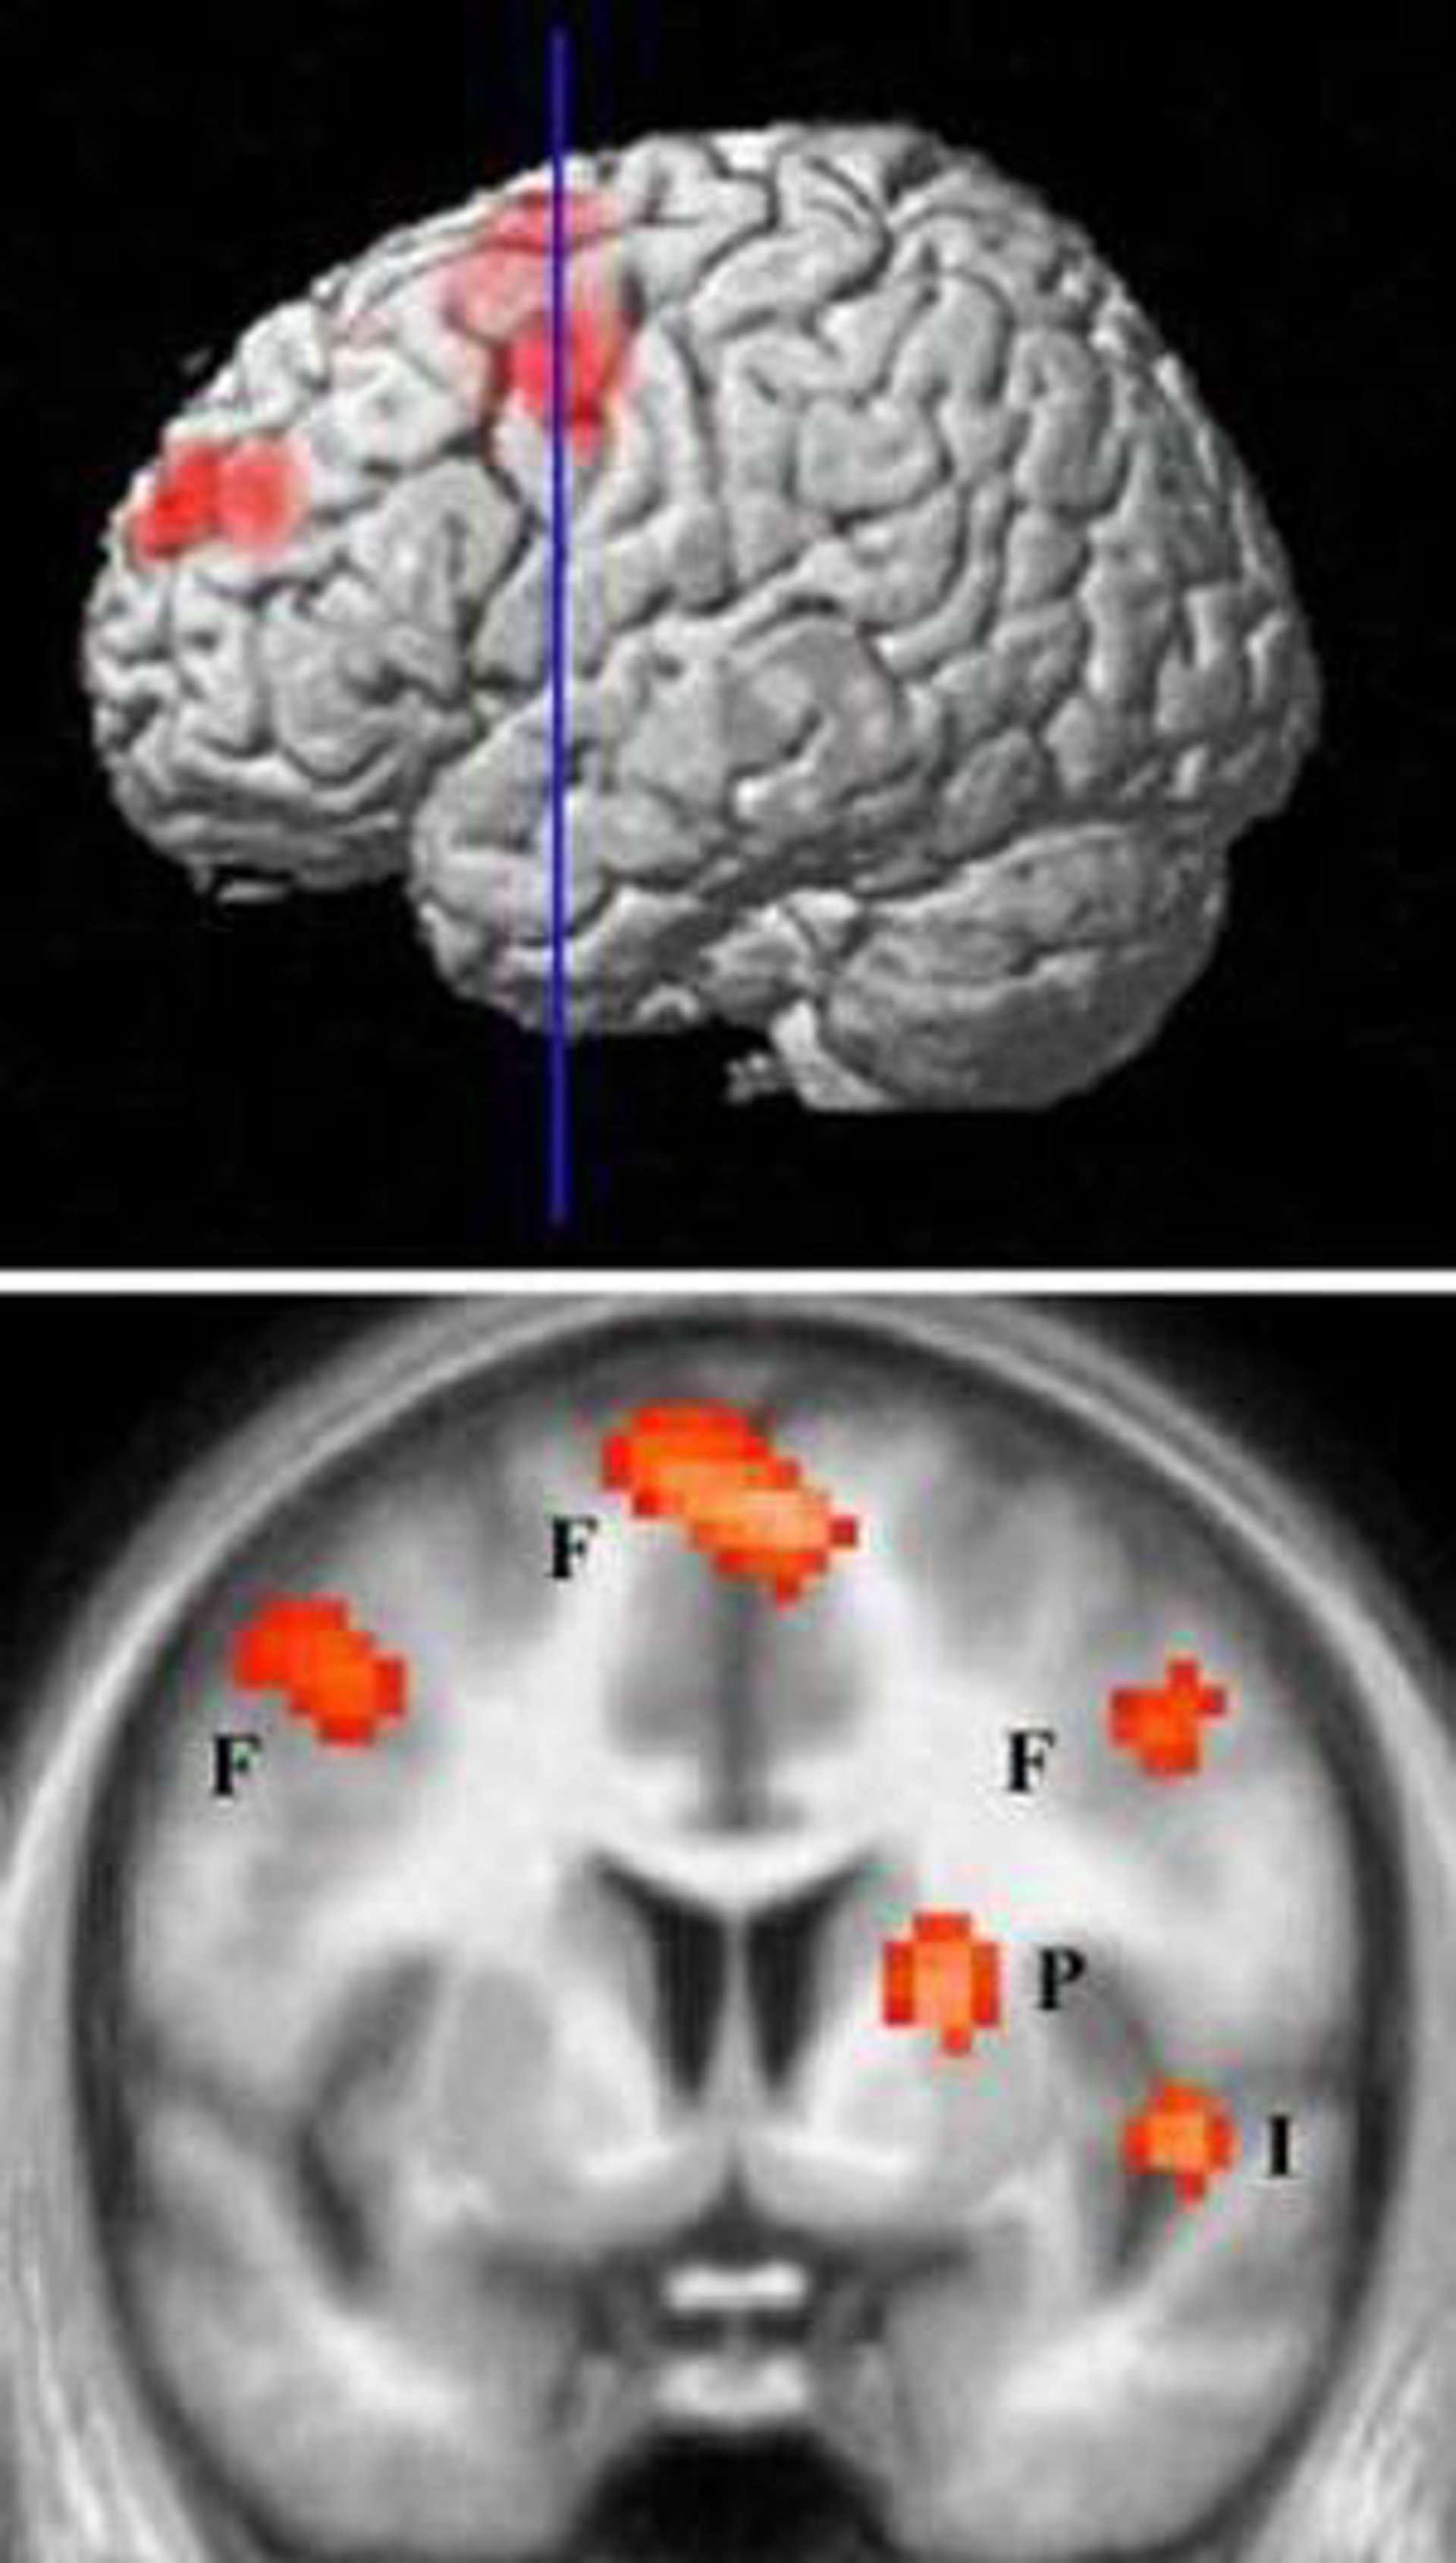

La enfermedad de Huntington es un trastorno que se caracteriza por la muerte de las neuronas en una región del cerebro denominada estriado, que tiene un importante papel en la planificación ejecución de los movimientos.

Los investigadores utilizaron ratones que expresaban formas mutantes de la proteína para evaluar el efecto sobre las neuronas de diferentes dosis del fármaco memantina. Este medicamento inhibe los receptores NMDA del cerebro, que son un subtipo clave de los principales receptores excitatorios del cerebro.

Los resultados mostraron que una dosis baja de memantina bloqueaba los receptores NMDA que se encontraban fuera de la sinapsis y que por ello reducía la gravedad de la enfermedad de Huntington en los ratones, como la muerte neuronal y el deterioro conductual.

Por el contrario, los investigadores descubrieron que una dosis elevada de memantina que bloqueaba los receptores NMDA que estaban tanto en la sinapsis como fuera de ella disminuía el número de acúmulos de huntingtina y empeoraba la enfermedad.

Los científicos también muestran que la localización de los receptores de NMDA en la neurona determina si su activación conducirá a la formación de agregados y la supervivencia de las neuronas o a la disolución de agregados y la muerte neuronal.